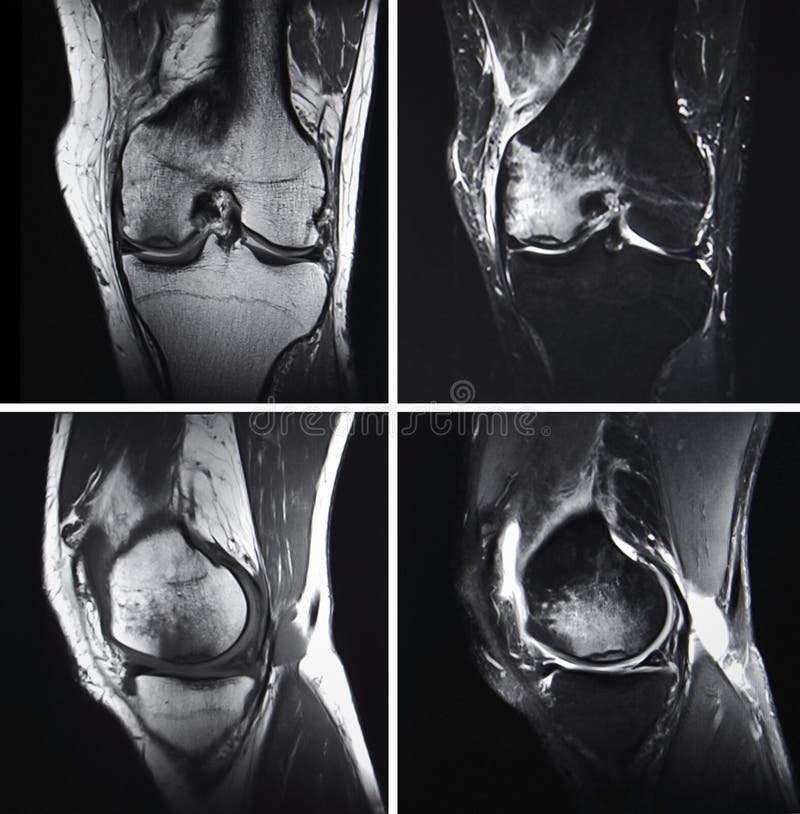

Injured knee, MRI stock image. Image of injury, tomography 34481207 Best Imaging For Knee Injury “trauma is when imaging is needed more. Magnetic resonance (mr) imaging of the knee has become the most commonly performed musculoskeletal mr examination and is an indispensable tool in the appropriate management of the. But what they are, and why you’d have one rather than another, isn’t always so obvious. Most of us can name the four main scans we. Best Imaging For Knee Injury.

Best Imaging For Knee Injury . With that in mind, here’s a brief guide to the four key kinds. Imaging modalities used to evaluate adults with acute knee pain and the appropriateness of particular imaging studies in. Most of us can name the four main scans we use to investigate knee problems: But what they are, and why you’d have one rather than another, isn’t always so obvious. “trauma is when imaging is needed more. Magnetic resonance (mr) imaging of the knee has become the most commonly performed musculoskeletal mr examination and is an indispensable tool in the appropriate management of the.